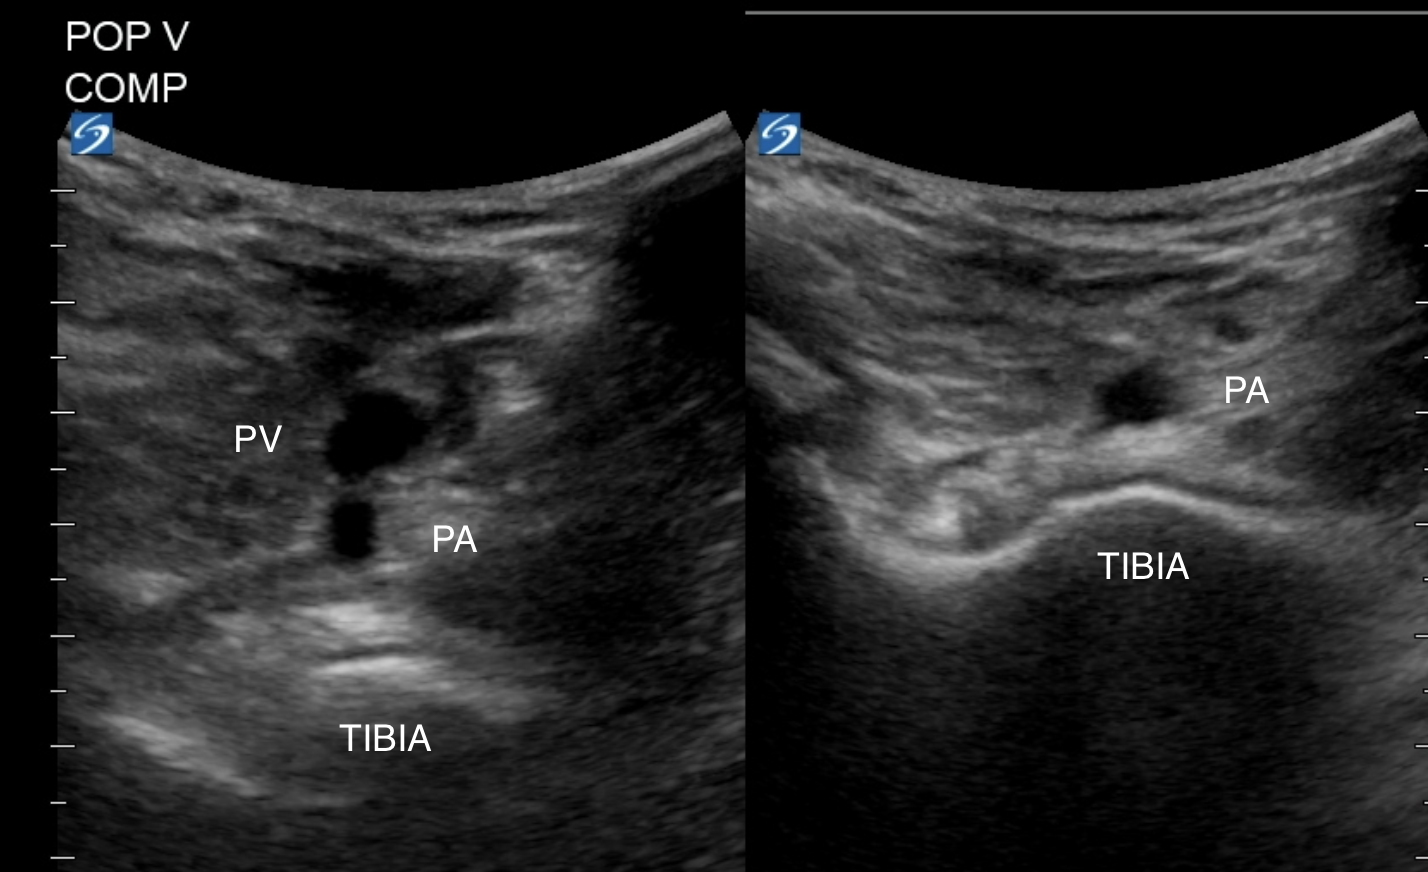

POPLITEAL VEIN

To image the popliteal vein, flex the patient's hip and knee and image posterior to the knee in the popliteal fossa, the probe in transverse, the probe marker to the patient's right.

On the screen you will see the vein superficial to the popliteal artery and the tibia. Compress with upward pressure against the tibia. Fan cranially and caudally to image as much of the popliteal vein as possible.